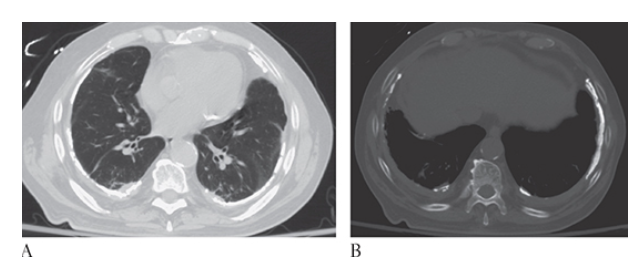

Pericardial Effusion. Contrast-enhanced CT (CECT) shows increased fluid density around the heart consistent with a pericardial effusion.

Pericardial Effusion. Normal for comparison.

What is A

Situs Inversus. CT axial and coronal multiplanar reconstruction (MPR)

What is B

Situs Inversus. CT axial show the heart apex on the right.